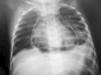

Figura 1. Radiografía de tórax posteroanterior, en donde se aprecia aire que rodea a la silueta cardíaca.

Varón de 2 años, indígena, con clínica de 3 meses de evolución de tos intensa, frecuente sin cianosis, inapetencia y pérdida de peso. Cinco días antes del ingreso se asocia fiebre y disnea. Antecedentes familiares de tuberculosis. Sin inmunizaciones. Peso para la talla: 3 DE, con signos clínicos de desnutrición. Temperatura: 37 °C. Sin cicatriz de BCG. Frecuencia respiratoria: 52/min. Tiraje subcostal. Murmullo vesicular, disminuido en base izquierda con soplo tubárico. Ruidos cardíacos rítmicos, hipofonéticos, frecuencia cardíaca: 110/min, sin signos de insuficiencia cardíaca. Radiografía de tórax: imagen de pneumopericardio, infiltrado neumónico y reacción pleural izquierda (fig. 1). PPD y BK en esputo seriado: negativo. Tomografía de tórax: imagen de pneumopericardio y en parénquima pulmonar: proceso inflamatorio bilateral, cavidades néumicas, derrame pleural bilateral a predominio izquierdo y adenopatías axilares. Radiografía de tórax: (control) pericardio engrosado y fístula broncopleuropericárdica. Control tomográfico: neumopericardio importantemente disminuido, engrosamiento pleural bilateral a predominio izquierdo (fig. 2). Al ingreso se indica antifímicos (isoniazida, rifampicina, piracinamida) y cefotaxima, la evolución fue satisfactoria, egresa a los 33 días, con resolución del pneumopericardio, ganancia de peso (1.200 kg) y tratamiento ambulatorio.

Cuando la presión intrapericárdica alcanza 265 mmH2O ocurre el taponamiento 8, en este caso no se presentó, aunque radiológicamente había una gran distensión del saco pericárdico (fig. 1).

En una radiografía simple de tórax, se observa una banda radiotransparente que rodea a la silueta cardíaca, que puede variar al movilizarse el paciente, hecho que sirve para diferenciarlo del neumomediastino y la tomografía permite identificar con precisión la presencia de aire en los diversos órganos torácicos, así como identificar la posible causa del cuadro clínico 9. En este caso el diagnóstico fue radiológico, corroborado por tomografía, apreciándose además fístula pleurobroncopericárdica.